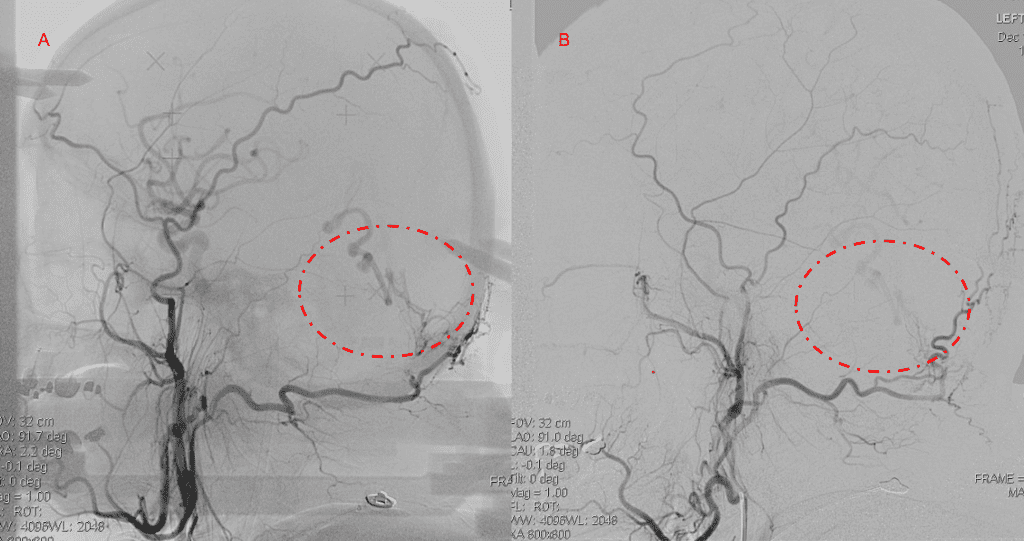

Figure 6. MRI and Catheter Angiograms precisely localize the residual A-V shunts vessels to perform Gamma-Knife Radiosurgery to deliver therapeutic doses to the targets.

Embolization was successful at immediately reducing the pressure into the Aneurysmal Varix with greater than 90% reduction in A-V shunts. After an intensive period of critical care monitoring and care for her initial brain hemorrhage, she made a near complete recovery with mild intermittent left sided paresthesias and generalized deconditioning. After receiving inpatient and outpatient Acute Rehabilitation, Physical, and Occupational therapy, she completely recovered all of her Activities of Daily Living (ADLs) at 3 months and achieved an modified Rankin Scale (mRS) of 0. On follow-up angiography, small residual low flow A-V shunts were identified and targeted for Gamma Knife Radiosurgery (Figure 5 and 6).